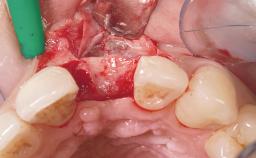

A 33-year-old female patient presented with an upper left central incisor that required extraction after a failed endodontic therapy. The tooth had been traumatized when the patient was a teenager and had undergone several endodontic treatments, including two apicectomy procedures. The patient was in good health and did not smoke. Clinical examination showed that the patient had a high lip line. In full smile, the gingival margins of the upper teeth were visible to the first molars. The gingival margins of central incisors 11 and 21 were only just showing. Examination of tooth 21 confirmed that the tooth was mobile and had hypererupted by 1 mm.

Bone Augmentation Horizontal|Simultaneous

Augmentation Materials Xenogenous|Membrane

Soft Tissue Grafting Simultaneous